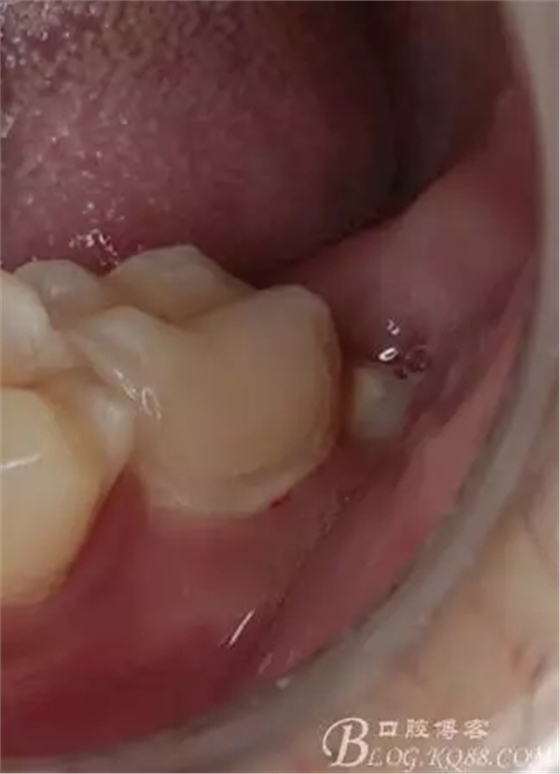

第四次復(fù)診,37叩(—)。此次行冠部修復(fù),因涉及38的拔除,患者不愿拔除,與患者介紹修復(fù)材料與方法,擬37E.max嵌體修復(fù),術(shù)前常規(guī)簽修復(fù)知情同意書。

去除暫封物,拍照,比色。